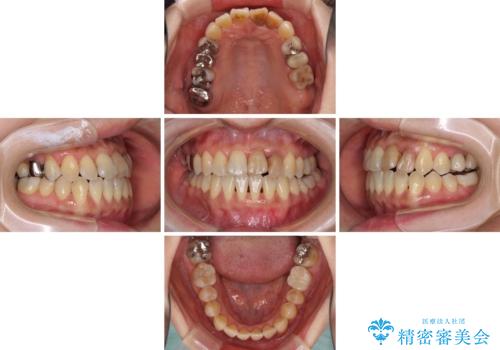

反対咬合で痛む前歯を改善 インビザラインによる矯正治療

- 前歯の反対咬合により、日々強い痛みを感じているとのことで来院された患者様です。

骨格的に下顎が前方位にありますが、歯列矯正で前歯の被蓋関係を改善することができると判断されたため、インビザラインにより矯正治療を行うこととしました。

また、上顎前歯と下顎大臼歯に神経を取り除いた歯があったため、矯正治療後に、セラミッククラウンにて補綴することとしました。

前歯が内側に倒れ込む力がかかり、正常な歯ぎしりもできないため、非常に負担のかかりやすい咬み合わせでした。

矯正治療中に上顎前歯が下顎前歯を乗り越える際は、前歯でしか咬めない状況が続くため、食事など不便を感じましたが、治療後には前歯の痛みもなくなり、安定した咬み合わせとなりました。